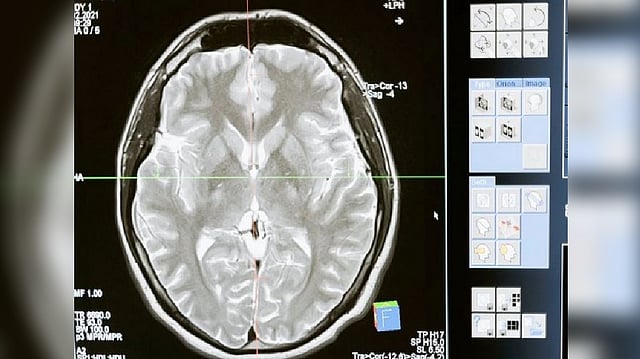

Representative image

CALIFORNIA: A research team led by the University of California, Irvine has discovered a relationship between Huntington's disease mutation and developmental deficits in the brain's oligodendrocyte cells brought on by irregularities in metabolism. They found that high doses of biotin and thiamine can bring normal functions back.

OL cells generate the insulating coating around neurons, called myelin. The study, published online in the journal Nature Communications, provides detailed insight into the entire process of how these changes in the genes that regulate cell metabolism impair the development of OLs, as well as the therapeutic value of treating HD with high doses of thiamine and biotin. Thiamine and biotin are both B vitamins and are involved in a wide range of metabolic processes that help keep the nervous system healthy.

Using advanced modeling methods, researchers confirmed that in mouse and human HD brain tissue, the maturation state of OL cells and their precursors are arrested in intermediate development, impairing production of the myelin that is critical for neuronal health and function. They found that high doses of thiamine and biotin were connected to significant rescue of gene expression changes in OL cells.